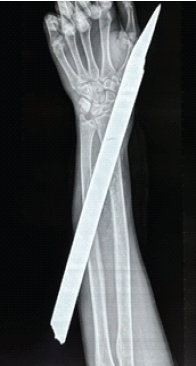

The Clean Pass: Upper Limb Impalement with Complete Neurovascular Preservation

Rajath S Shetty , Aditya A Agarwal , Sangram A Yadav , Priyanka Meena , Susovan Mandal , Chandrashekhar R Rai

………………………………p.168-172